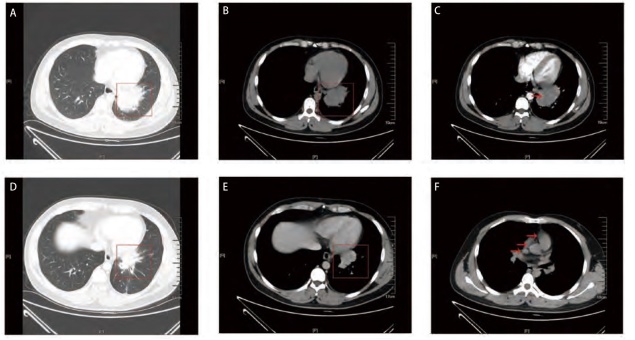

Results: A total of 14 cases of PPLEC were identified, including 5 cases of the Regaud type, with ages ranging from 33 to 73 years, comprising 2 males and 3 females; and 9 cases of the Schmincke type, with ages ranging from 36 to 79 years, including 4 males and 5 females. Computed tomography (CT) scans consistently demonstrated soft tissue masses or nodular shadows. Reagud type mainly showed peripheral masses and Schmincke type mainly showed central masses. Pathological examination revealed tumor cells exhibiting syncytial-like growth, accompanied by lymphocytic infiltration and stromal fibrosis, with the Regaud type showing well-defined borders combined with granulomatous inflammation, while the Schmincke type exhibited indistinct tumor margins. Immunohistochemistry showed that CK, CK5/6, P40 and P63 were positive, and the Ki-67 index of Regaud type was lower than that of Schmincke type; notably, all 8 cases tested for programmed death-ligand 1 (PD-L1) were positive. Epstein-Barr virus-encoded RNA (EBER) in situ hybridization was positive in all instances. Among these cases, 6 underwent surgical treatment, and 8 received comprehensive therapy; by the end of the follow-up period, all 14 patients remained alive.